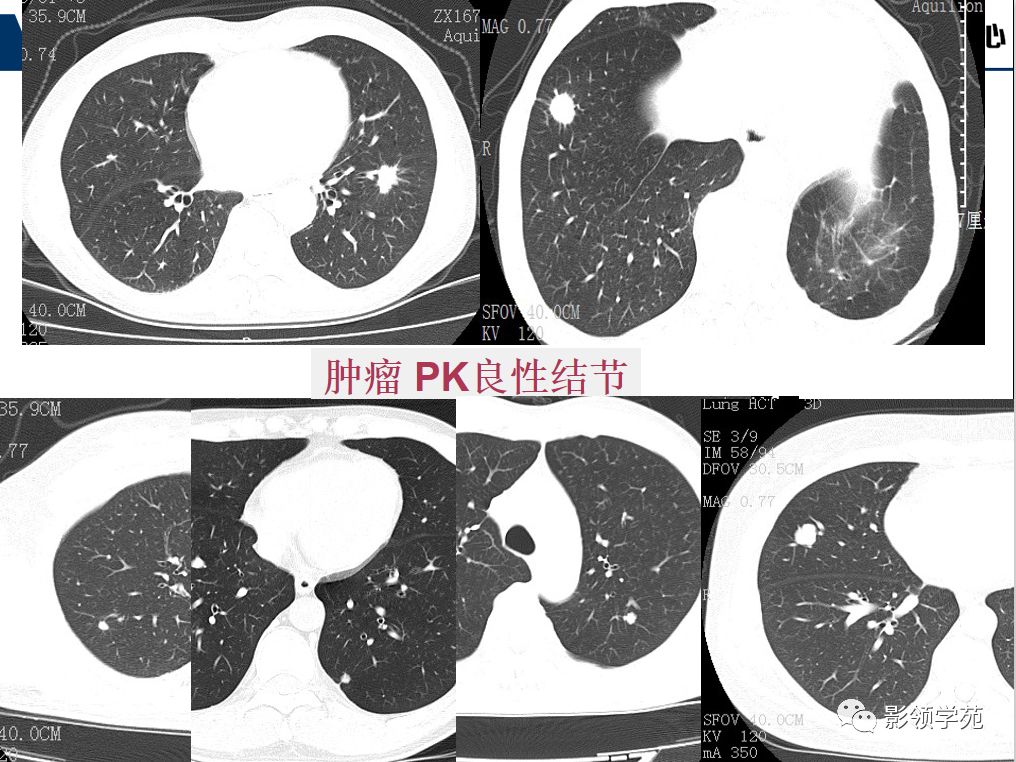

肺良恶性结节ct征象及鉴别诊断

实性肺结节的良恶性ct征象解析